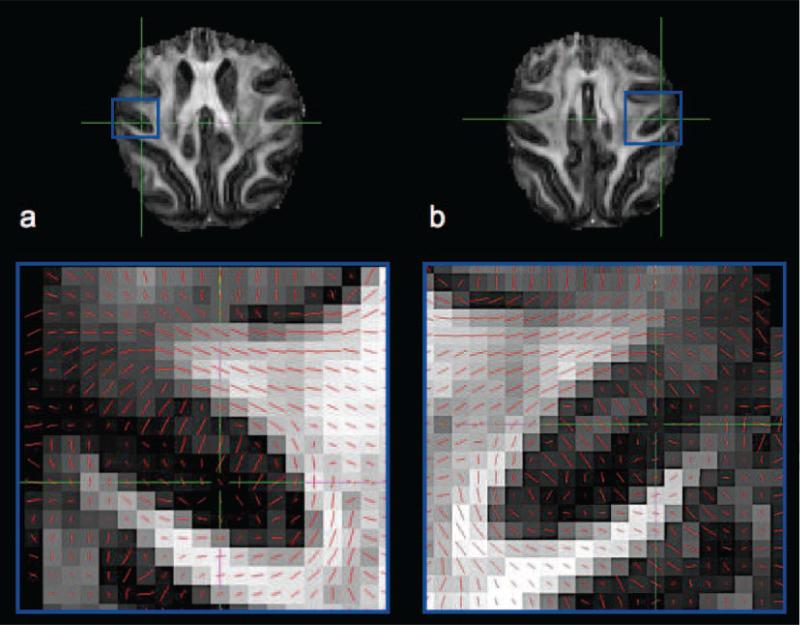

Figure 1 shows a subset of the in vivo human 1 mm isotropic DTI data for one subject. The FA and directionally encoded color (DEC) maps (Fig. 1a and b) exhibit high SNR and low levels of distortions. Figure 1c shows an axial slice of the FA map in region surrounding the central sulcus with the principal eigenvector of the diffusion tensor superimposed using line representations. The principal eigenvector in cortical voxels anterior to the central sulcus (i.e. M1) appears radial while those in S1, located posterior to the central sulcus, appear tangential. Still, it is difficult to fully appreciate the cortical diffusion anisotropy relative to the highly convoluted geometry of the cortex using the traditional slice representation.

FIG. 1.

DTI from one subject including a) a fractional anisotropy map (coronal), b) a directionally-encoded colour map (coronal) and c) principal diffusion orientations (red lines) superimposed on FA map in the region of S1 and M1 (axial).